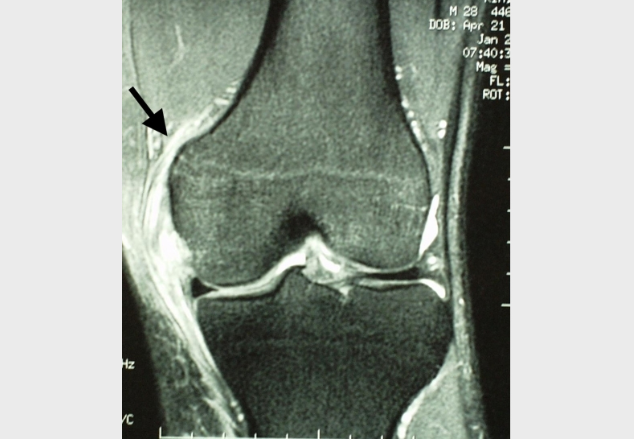

Image from OpenI – Licensed by CC